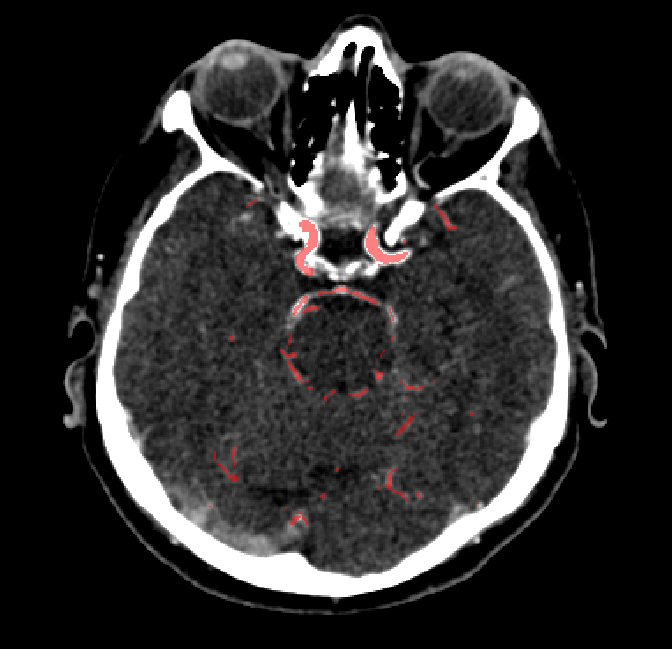

After fine-tuning, the two pre-train conditions appear to have little or no difference in terms of qualitative performance at the vessel segmentation task. However, when compared to the models trained only on real data, there are noticeable differences. Throughout Figures 4.3-4.9, the model pre-trained on scans with original CT noise is to be taken as representative of segmentation performed by the Perlin noise pre-training condition. Images showing the hand-labeled ground truth, as well as the unlabeled slice, are presented for comparison.

Figure 4.3: Segmentation on internal carotid arteries. Unaltered image (left). No pretrain model (mid-left). Fine-tuned model (mid-right). Hand-labeled ground truth (right).

In the other hand, it should be noted that fine-tuned models suffered from false positives more often than models with no pre-training. The fine-tuned models appeared to occasionally segment regions near the skull, which although similar in intensity to vessels, had no resemblance in terms of shape. Examples of this are seen in Figure 4.4 near the occipital bone and near the right temporal bone. Examples of oversegmentation were observed to happen commonly around the internal carotid arteries. This is likely due to the amount of contact surface between the artery and the surrounding bone. There was also a tendency for all model conditions to segment bone regions that were similar in shape to large vessels (Figures 4.3 and 4.4). Bone structures in such regions have similar pixel intensities to the arteries transporting contrast material, which could explain the source of confusion for a model.

To our surprise, the models were able to occasionlly segment the shape of the internal carotid arteries correctly despite no boundary being visible to the naked eye between the vessel wall and the surrounding bone structure. An example of this can be seen in the fine-tuned model in Figure 4.3.